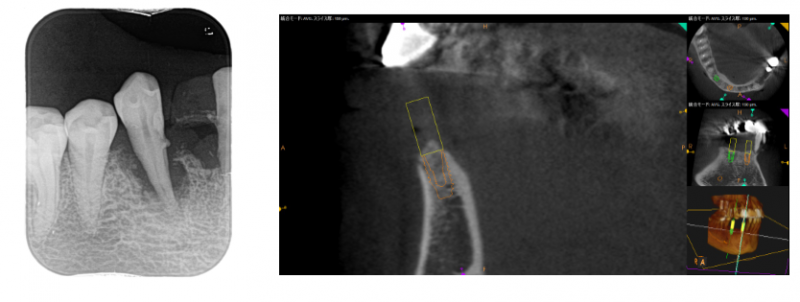

歯周病で抜歯になったケースです。

抜歯後、数ヶ月骨の治癒を待ち、CT診査しました。

骨幅が狭いのと、インプラントブリッジで平行性が求められるため

ガイドを使って埋め込みする計画にしました。